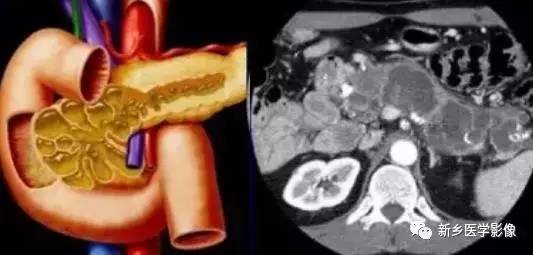

2、影像学诊断:

主胰管型的病变C T 、M RI 上可表现为主胰管囊状扩张,其主要分支也可见扩张,胰腺萎缩, 有时与慢性阻塞性胰腺炎难以鉴别, 如果显示了扩张胰管内的壁结节或黏液栓对诊断颇有帮助, 薄层扫描及变换体位对显示壁结节和黏液栓有好处, 黏液栓随重力总位于囊腔下壁。

位于胰头部的病变还可引起扩张的壶腹突向十二指肠腔。发生于胰管分支的病变表现为多房状囊性肿块, 常位于胰头钩突, 内可见间隔, 表现与囊腺瘤相似, 后期病变累及主胰管则出现主胰管的扩张及其腔内的壁结节和黏液栓。